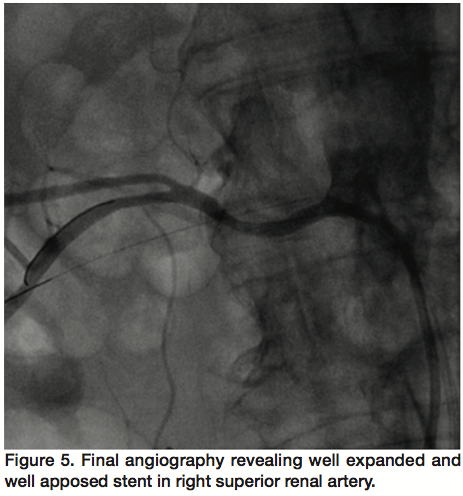

Based on these results, simultaneous percutaneous intervention of both right renal arteries was performed. After obtaining access in both common femoral arteries, two 7 Fr Renal Double Curve guide catheters (Cordis Corporation) were simultaneously engaged into the 2 renal arteries. We gave the patient 7000 units of heparin intravenously, which resulted in an activated clotting time of 276 seconds. We placed 0.014-inch diameter Asahi prowater guidewires (Abbott Vascular) distally and crossed the stenosis in each renal artery. Using two 2.5 mm x 8 mm Quantum Apex non-compliant balloons (Boston Scientific), simultaneous kissing balloon angioplasty of both renal arteries was performed at 12 atm (Figure 3). However, the lesion in the superior renal artery failed to yield, requiring another angioplasty at 20 atm using the same balloon. Subsequently, serial stenting of the 2 renal arteries was performed using 2 Liberté Rx bare metal stents (Boston Scientific): 3.5 mm x 12 mm for the superior and 3 mm x 12 mm for the inferior renal artery. Final angiography revealed well-expanded stents in both renal arteries with <20% residual stenosis in the inferior (Figure 4). There was no residual stenosis in the superior renal artery (Figure 5). There was no distal embolization, and no dissection.